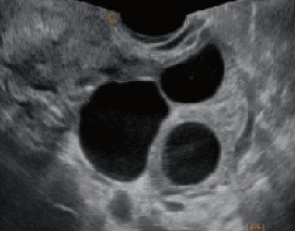

- Este modelo Cbit 6 contiene tecnología de alta gama con procesadores de transmisión mejorada logrando una señal más fluida, esto te permitirá obtener unas imágenes de mayor calidad y más precisas.